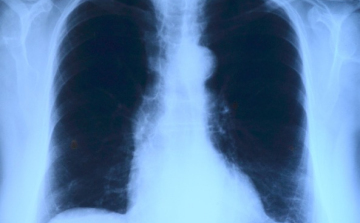

Elvégezték az országban az első tüdőverőér-tágítást

Az országban elsőként a Debreceni Egyetem Klinikai Központjában végeztek tüdőverőér-tágítást - közölte a felsőoktatási intézmény sajtóirodája kedden az MTI-vel.

Már a 26. tüdőátültetést végezték el Magyarországon

A 26. tüdőátültetést végezték el Magyarországon a közelmúltban - közölte az Országos Onkológiai Intézet és a Semmelweis Egyetem hétfőn az MTI-vel.

Az anya és az apa is adott a tüdejéből

Apja és anyja is adott a tüdejéből egy-egy részt egy 15 éves lánynak, miután kiderült, hogy mindketten jók szervdonornak a krónikus beteg számára.